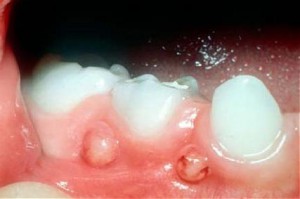

Пародонтальний абсцесс представляет собой серьезное стоматологическое заболевание, которое сопровождается воспалением десны, и происходит гнойное образование в тканях пародонта.

Выглядит это как воспаленное округление в области зуба, а вырасти может в размере как грецкий орех.